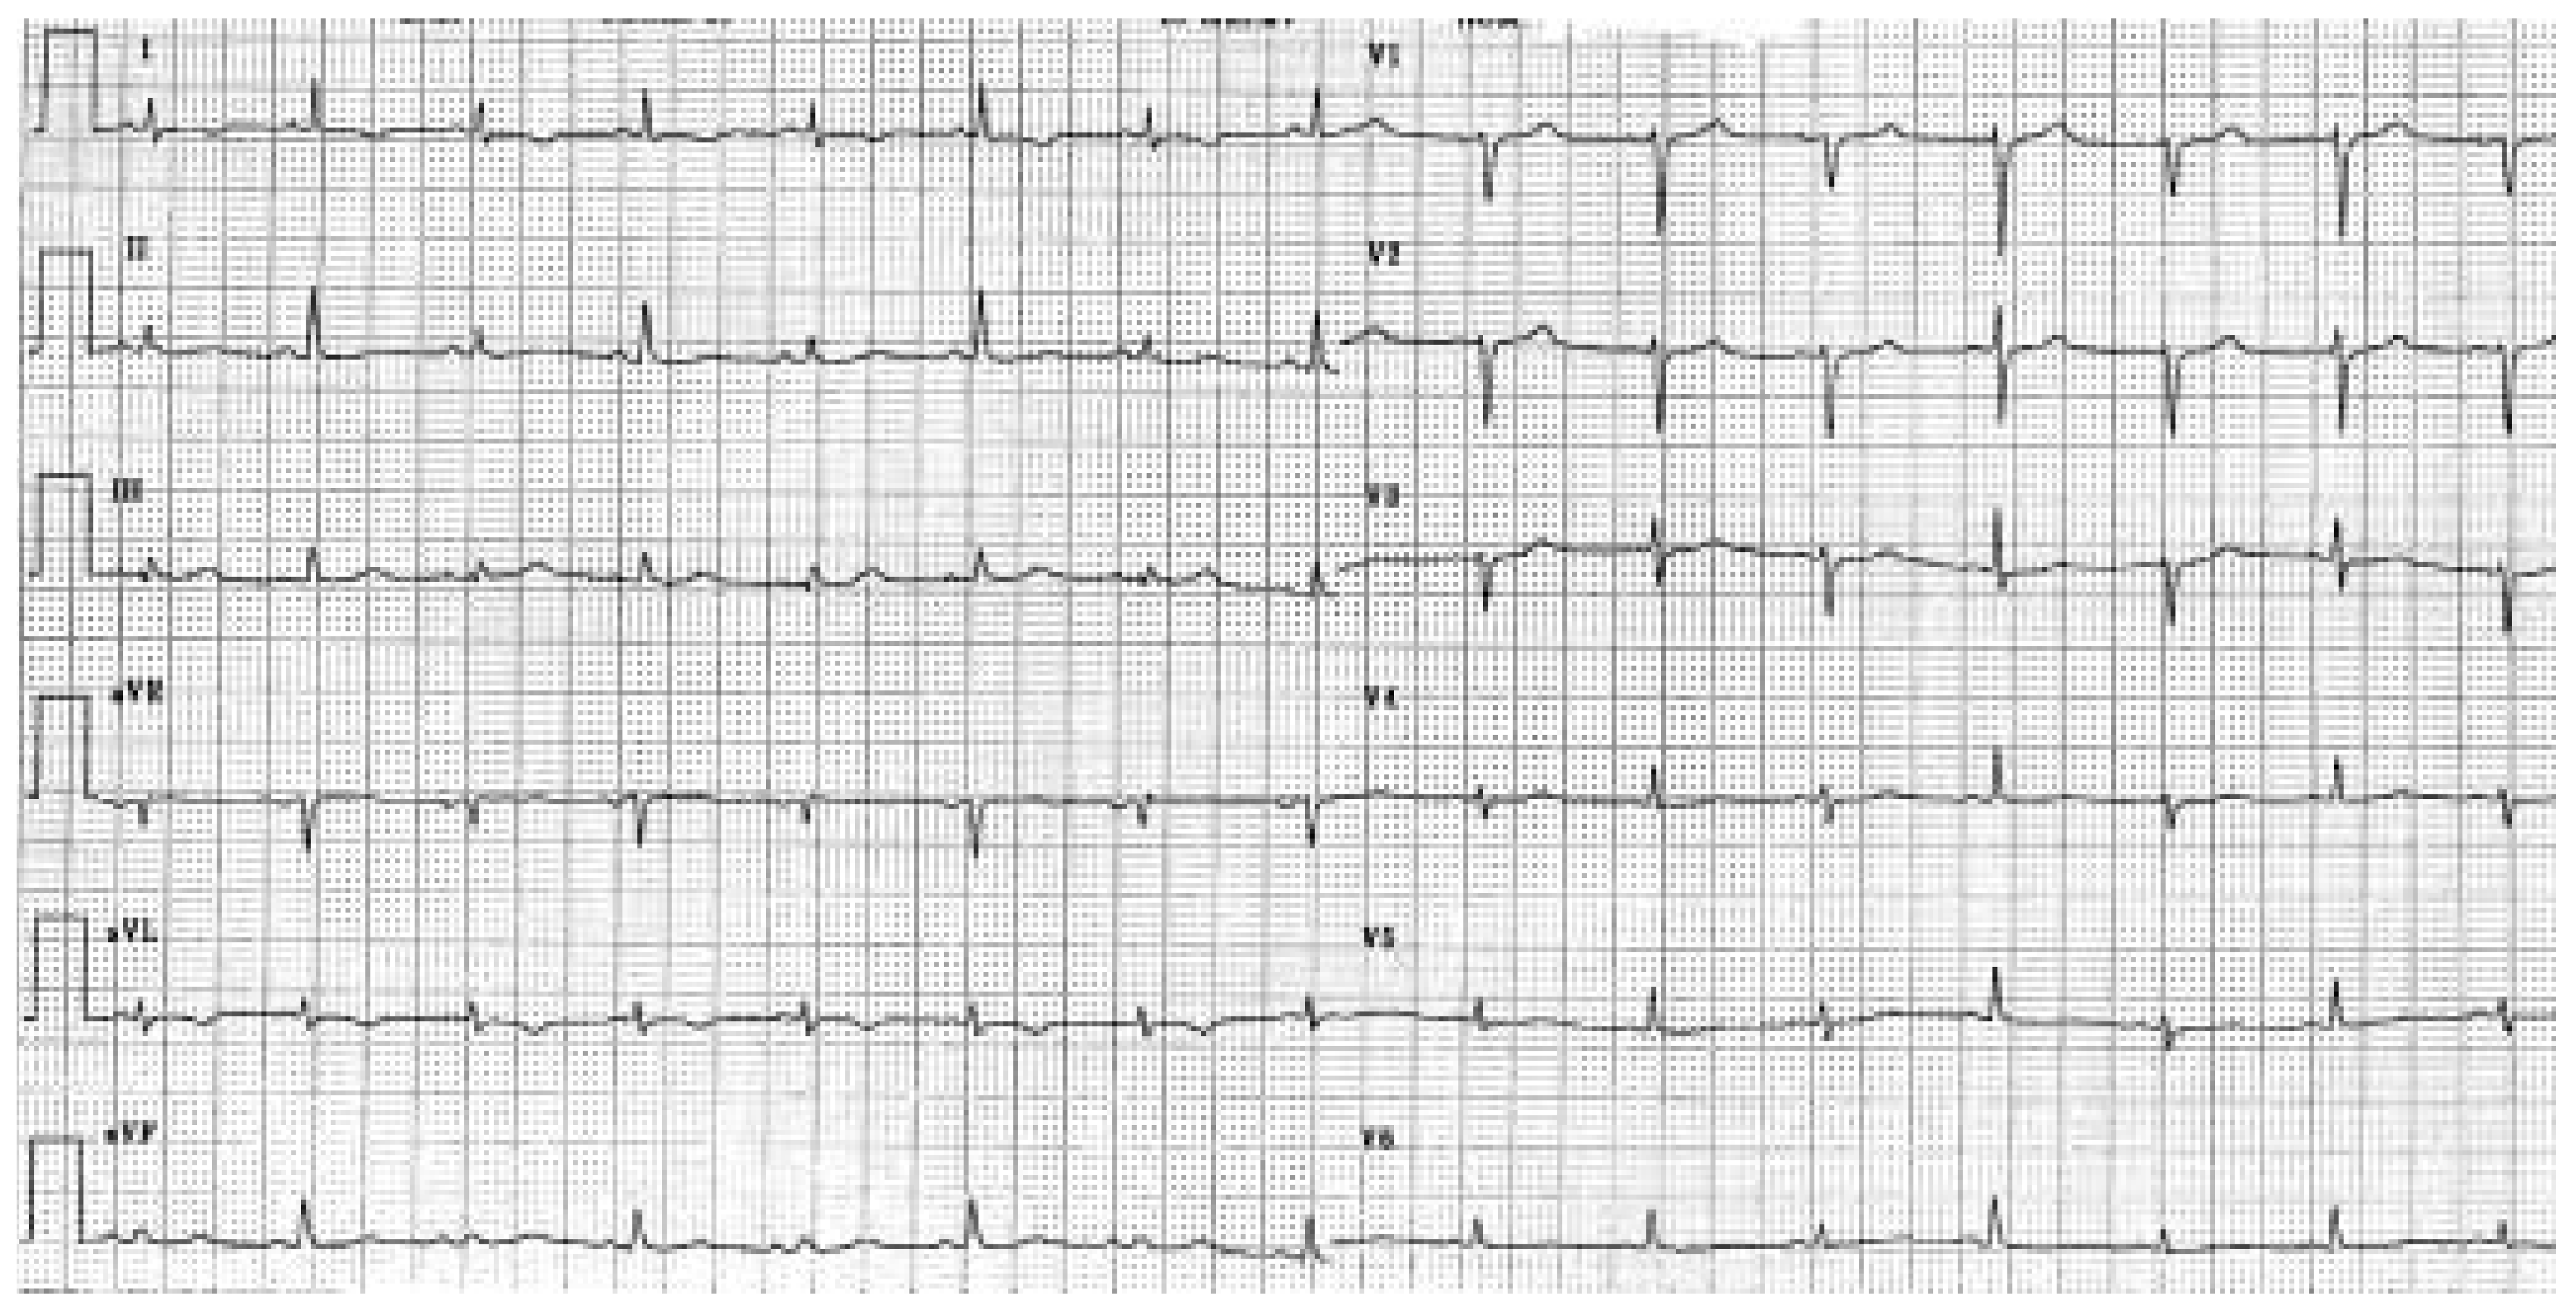

Epanchement Péricardique

Description du cas

Commentaires